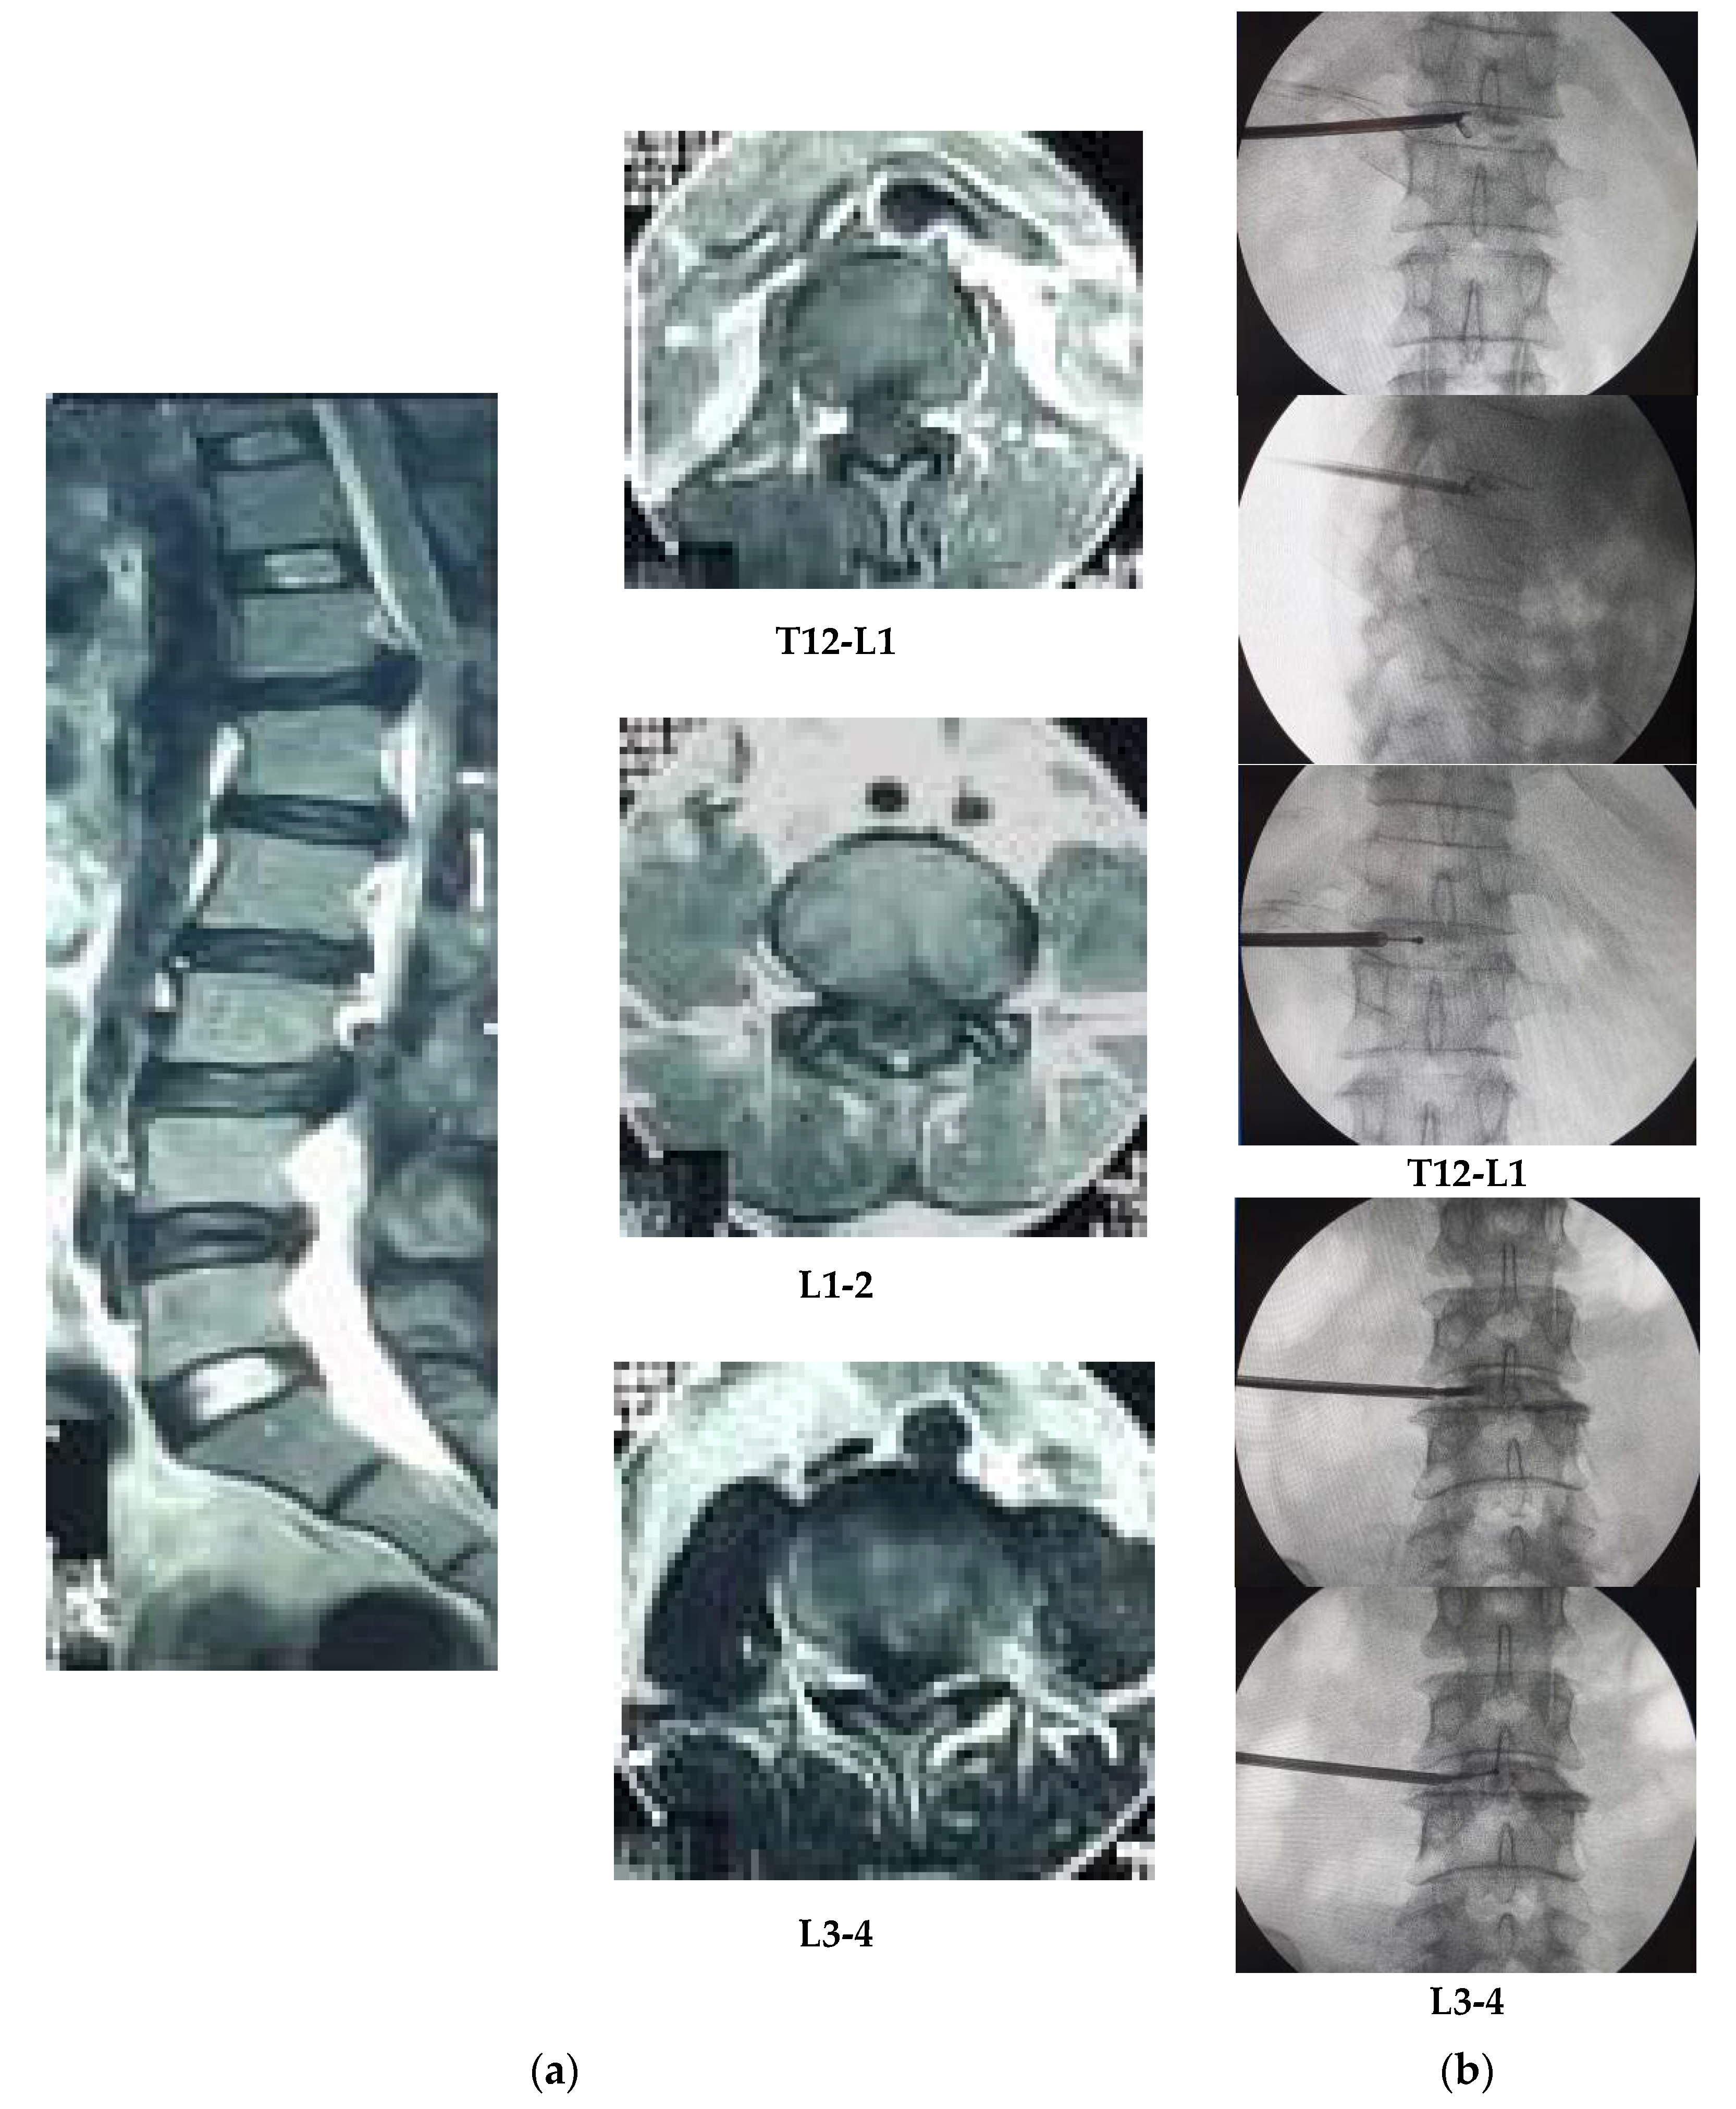

Figure 2. (a) Magnetic resonance imaging (MRI) result of patient #1: posterocentrally protruded disc at L3-4, bulged discs at L4-5 and L5-S1 level and the compression slightly to the left side by axial view; (b) according to the lesion site dilator canula placed near to the L3-4 neuroforamen (one-third portion between midline and lateral border of disc) by posteroanterior (PA) view, so discectomy and bipolar coagulation might be done carefully.